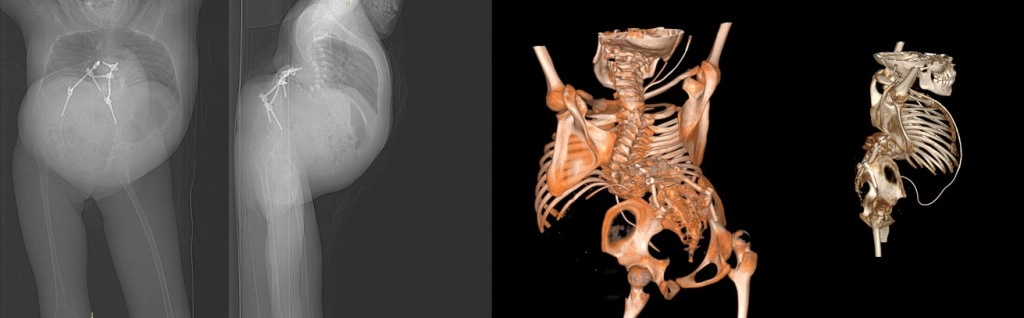

Девочка 14 лет

Поступила с жалобами на деформацию позвоночника, одышку, отсутствие движений в ногах, слабость в руках и периодическое истечение жидкости из свища в поясничной области

Ликворный свищ / Cerebrospinal fluid fistula

Диагноз:

Множественные врожденные аномалии головного, спинного мозга, позвоночника.

Тяжелый кифосколиоз грудопоясничного отдела позвоночника. Состояние после ВПШ. Артерио-венозная мальформация вены Галена. Аномалия Арнольда-Киари. Менингомиело-цистоцеле. Наружный ликворный свищ из зоны менингоцеле Th6-L1.

Нижняя параплегия. Верхний легкий парапарез.